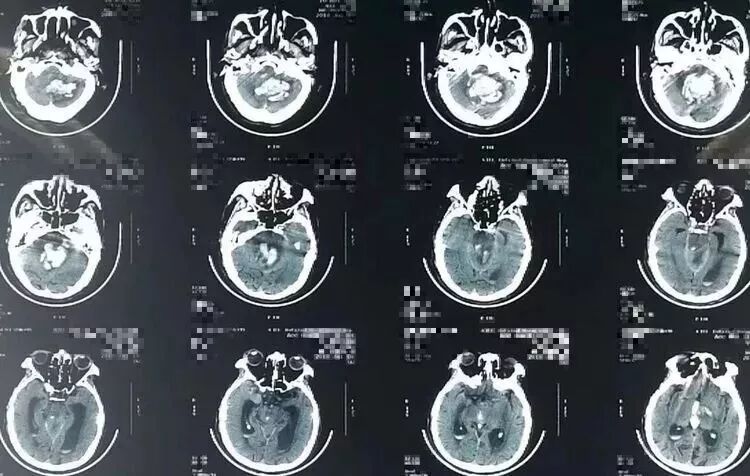

突发意识障碍3小时,既往有高血压病史数年。入院后病人自主呼吸,GCS=6,瞳孔正常。CT提示右侧小脑半球深部脑内血肿,破入IV脑室和III脑室。

术后病人生命指征稳定,瞳孔正常,自主呼吸正常,意识障碍较术前改善。复查头CT可见小脑内、IV脑室和III脑室内血肿清除满意。